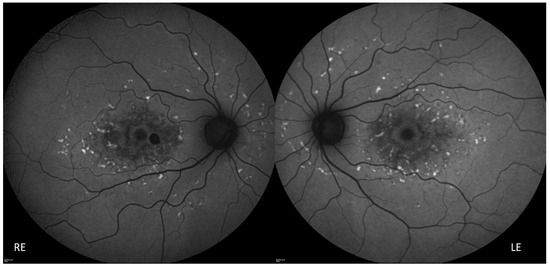

3.1. Clinical Features